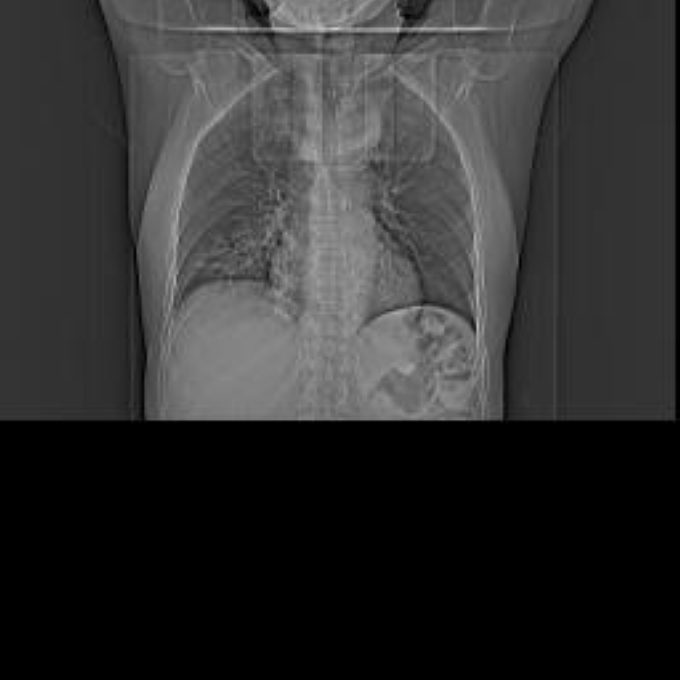

56 year old patient with dyspagia. A tumor of soft tissue was described in upper mediastinum on plain X-ray of the thorax. What is this mass in the upper mediastinum?